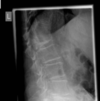

Fratura compressiva da coluna lombar

Causa achatamento do corpo e acunhamento geralmente anterior.

Tipo mais comum de fratura da coluna lombar

Estável.

Mecanismo flexão anterior ou lateral